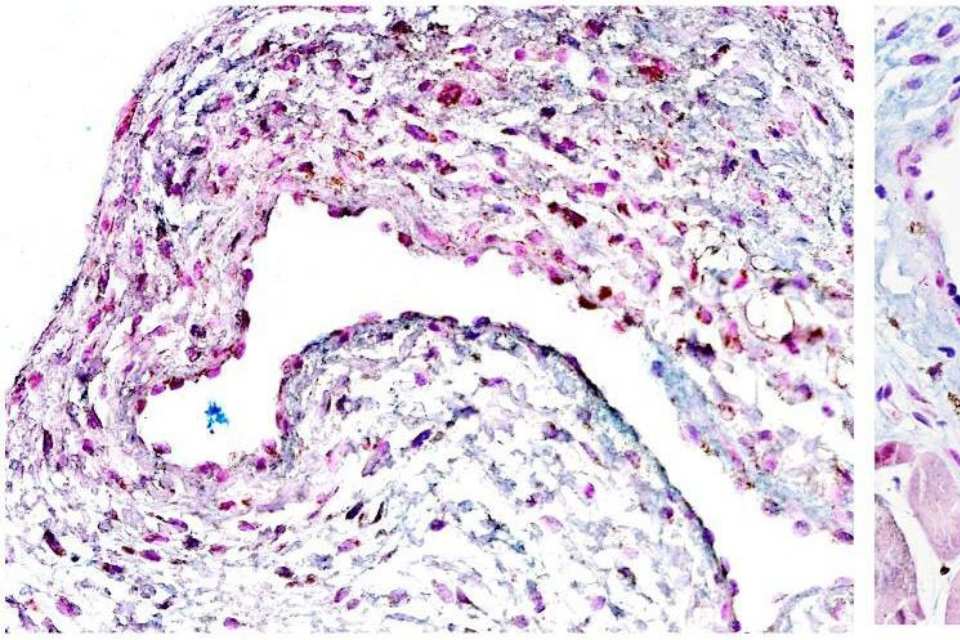

Investigadores de Mayo Clinic han descubierto que el trasplante de células madre derivadas de las propias células de grasa del paciente a la vena, ayudó con frecuencia a prevenir la inflamación y el estrechamiento venoso. Esto puede ayudar a millones de personas con enfermedad renal terminal a tolerar la diálisis por más tiempo, posponiendo la necesidad de un trasplante de riñón.

Esto se debe a que estas células madre adultas, llamadas células madre mesenquimales, secretan factores de crecimiento reparadores que parecen ser eficaces en determinados pacientes con FAV, según explica el Dr. Sanjay Misra, radiólogo intervencionista en Mayo Clinic y autor principal del estudio publicado en Science Translational Medicine.

En este estudio, 21 participantes recibieron fístulas arteriovenosas (FAVs) como parte de un ensayo clínico de fase 1. Once participantes recibieron inyecciones de células madre mesenquimales obtenidas de sus propias células grasas antes de la cirugía de FAV; 10 formaron parte del grupo de control. Las FAVs cicatrizaron más rápido y fueron más duraderas en la mayoría de quienes recibieron las células madre. Sin embargo, no todos respondieron al tratamiento.

Los investigadores identificaron factores genéticos específicos con acción antiinflamatoria en aquellos que respondieron bien a las células madre. Afirman que estos biomarcadores genéticos pueden ayudar a predecir qué pacientes tienen más probabilidades de beneficiarse de esta aplicación de células madre, así como ayudar a seleccionar opciones de tratamiento personalizadas. Los investigadores esperan obtener más información a través de ensayos clínicos a gran escala.